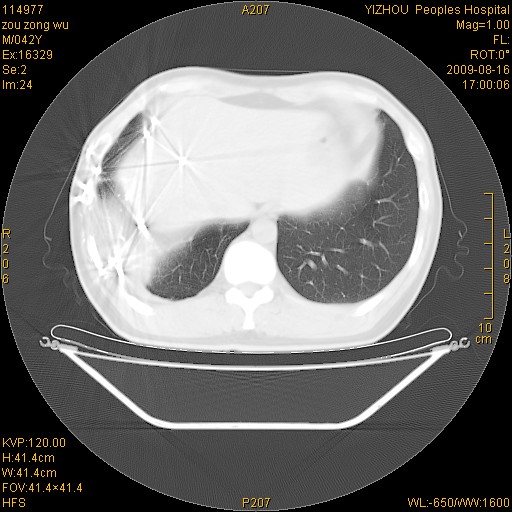

以下是引用zjzjr在2009-8-17 10:42:00的发言:[br]右侧间质性肺炎伴纤维化,右肺下叶肺囊肿伴感染(不除外外伤后引起),右肺野及胸壁软组织\\肝内见多发斑点状,中枪了吧.右侧胸膜肥厚\\粘连.